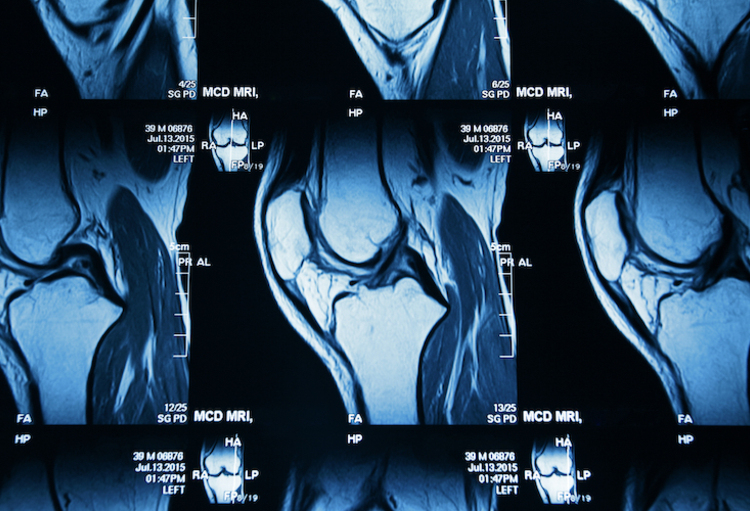

Traditioneel speelt de detectie van actieve sacro-iliitis een cruciale rol bij de vroege diagnose en monitoring van ontstekingsaandoeningen zoals spondylartritis. Maar het evalueren van MRI-scans van dit gewricht is een uitdaging vanwege de variabiliteit van inflammatoire laesies en de expertise die nodig is voor nauwkeurige interpretatie.

In deze nieuwe studie ontwikkelden onderzoekers van VIB-UGent en UZGent een computer vision-workflow om het hele proces te automatiseren, van het detecteren van het SI-gewricht en het segmenteren van de regio's tot het voorspellen van beenmergoedeem.

Het is een hele uitdaging om geautomatiseerde voorspellingen van ontstekingen te krijgen uit driedimensionale beelden van een complexe anatomische structuur, maar door het beeld in meer gedetailleerde secties te ‘segmenteren’ kan dit nieuwe algoritme de zoekruimte kleiner maken, wat tot betere voorspellingen leidt.